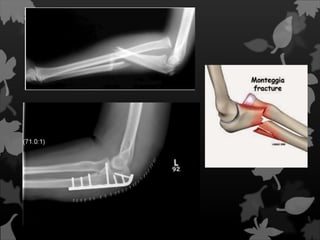

É uma fratura da ulna que afeta

a articulação com o rádio. Mais

precisamente, é uma fratura do

terço proximal da ulna com

deslocamento da cabeça do rádio.

Fratura de Monteggia Éuma fratura da ulna que afeta a articulação com o rádio. Mais precisamente, é uma fratura do terço proximal da ulna com deslocamento da cabeça do rádio.